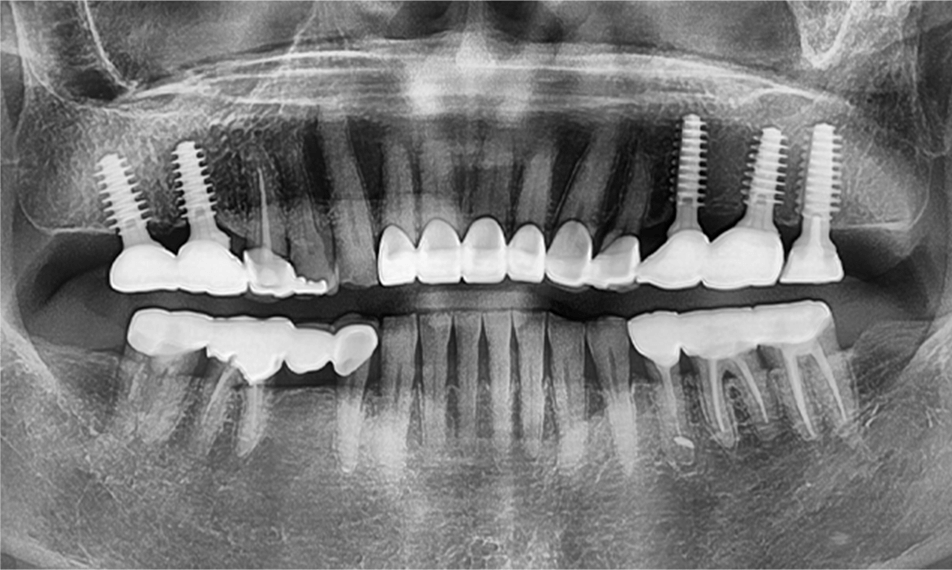

임플란트 치료

• before

• after